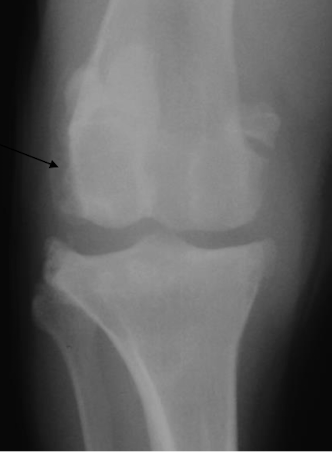

What is the arrow pointing to?

Enthesophyte